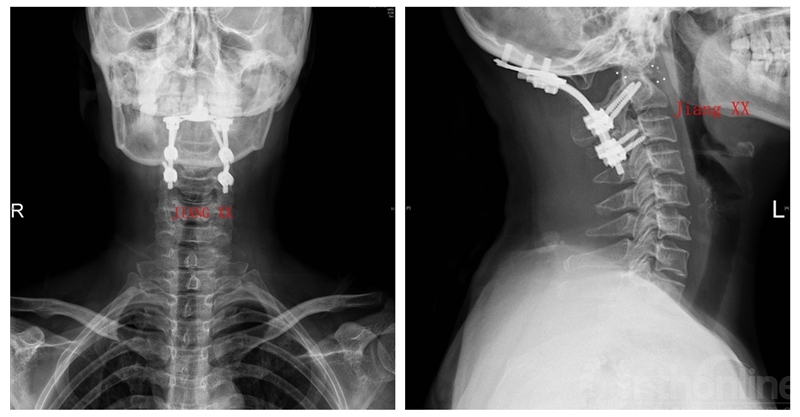

病例二:患者女性,58岁,主因“颈部疼痛伴转头受限半年”入院,诊断为寰枢椎半脱位。

术后X线